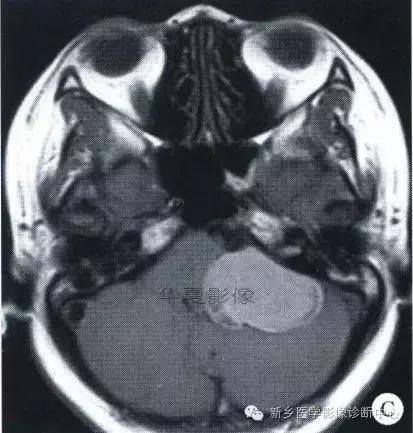

中枢神经系统内原发性黑色素瘤少见, 因脑和脊髓的软脑( 脊) 膜及蛛网膜上含有黑色素细胞, 黑色素可发生于软脑( 脊) 膜的任何部位,故其发生部位常位于脑( 脊髓) 表面, 沿软脑膜生长; 而继发性黑色素瘤同一般转移性肿瘤, 常位于灰白质交界区。

影像表现:常表现为短 T1 高信号, 短T2WI 低信号,又因为黑色素瘤是富血管性肿瘤, 增强扫描常表现为明显强化。

★但少数肿瘤也不具备上述典型信号特征,主要原因是肿瘤内黑色素量多少影响。只有当黑色素瘤中黑色素细胞超过一定含量( ﹥ 10% ) 时, 才会出现黑色素瘤的典型MRI表现; 不典型的黑色素瘤因其黑色素含量较少,不足以缩短T1、T2弛豫时间,而表现为长T1低信号、长T2高信号。

依据黑色素瘤的不同 MRI 影像表现将其分为 4 种类型: ( 1) 黑色素型。该黑色素瘤因含有丰富的黑色素颗粒, MRI表现较典型,即短 T1 高信号,短 T2 低信号。( 2) 无黑色素型。因该类黑色素瘤不含黑色素颗粒或含量较低,MRI 表现为长 T1 低信号,长 T2 高信号; ( 3) 混合型。黑色素型和非黑色素型两者的混合; ( 4) 出血型。表现为血肿不同时期的信号特征, 该黑色素瘤 MRI增强扫描表现为不均匀环状或弥漫性强化